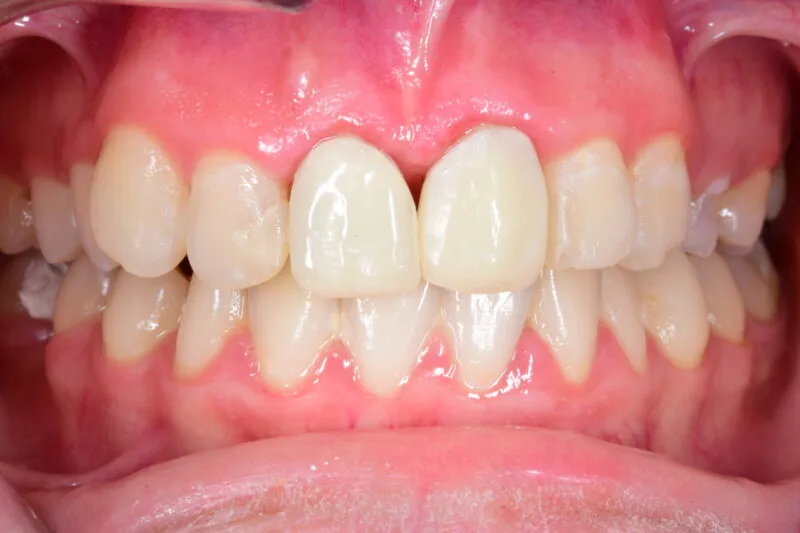

¿Notas que tus dientes parecen más largos que antes? ¿Te sangran las encías o sientes más sensibilidad al tomar algo frío o caliente? Todo esto puede deberse a un problema bastante común: las encías retraídas.

La retracción de encías ocurre cuando el tejido que cubre y protege la base de los dientes se va desplazando hacia atrás, dejando parte de la raíz dental al descubierto. Lo normal es que las encías recubran la raíz por completo, pero si se retraen, esa zona queda más sensible y expuesta.

El problema no es solo estético. La raíz del diente no tiene esmalte que la proteja, así que se vuelve más vulnerable a caries, sarro e infecciones. Además, con el tiempo, la retracción puede afectar al hueso que sujeta el diente y provocar sensibilidad o incluso movilidad dental.